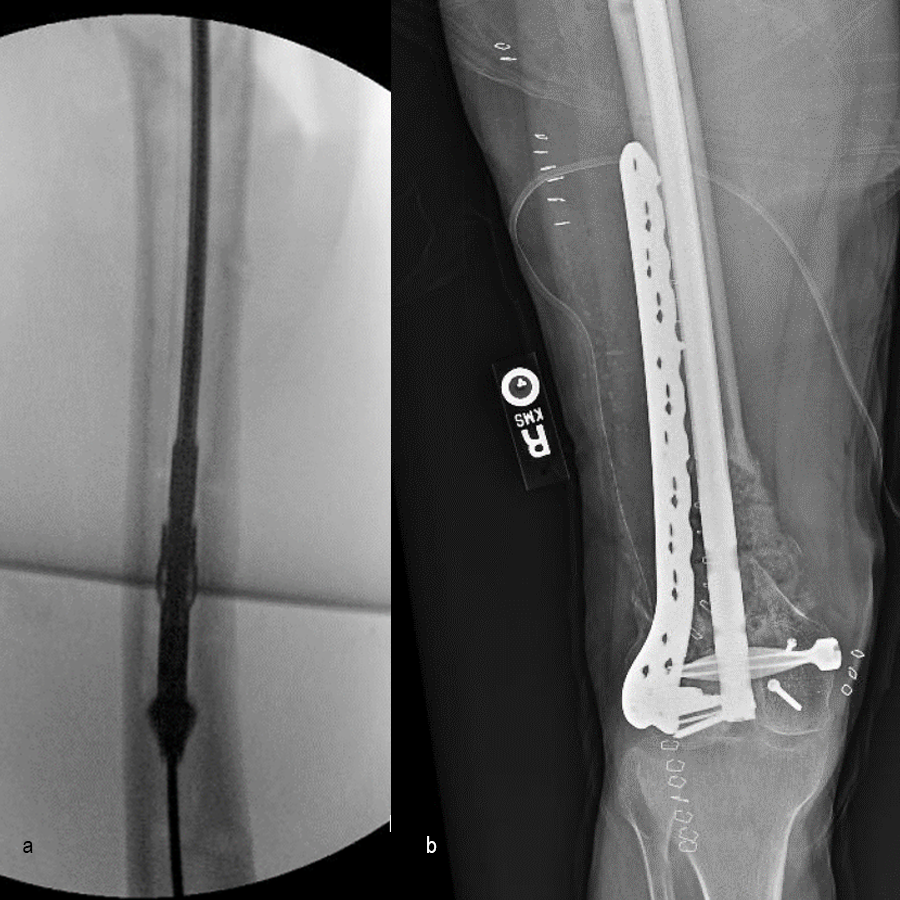

At the 3-week follow-up (post-graft cage, Fig 12), the patient’s wounds were healthy. He had a range of motion (ROM) of 0–80 in his right knee. He was allowed weight bearing as tolerated (WBAT) with crutches.

At the 3-month follow-up (Fig 13), the patient had a ROM of 0–120 in his right knee. His quadricep muscles had significantly recovered and he was able to WBAT with support from a cane.

At the 6-month follow-up (Fig 14), the patient was able to WBAT on the right lower extremity. He had some ankle pain and a ROM of 0–125 in his right knee. The patient was able to walk without any assistance device.

At the 9-month follow-up (Fig 15), the patient reported nominal knee pain, but more pain in his ankles. The patient had returned to work. He was not undertaking any heavy lifting but was driving the truck and supervising the team. Overall, the patient was happy with the current outcome of surgery.